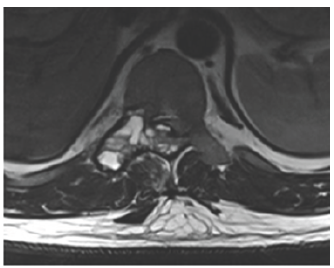

Thoracic MRI with gadolinium: heterogeneous cystic lesion (ballooning appearance) involved the posterior elements (right lamina, pedicle, facet joint) of T, narrowing of the spinal canal

With cord compression also noted (Figure 1- 3)

Figure 2: T2 MRI.

Figure 3: T2 axial view.